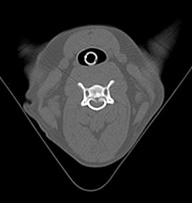

悪性腫瘍肺転移

• イメージ